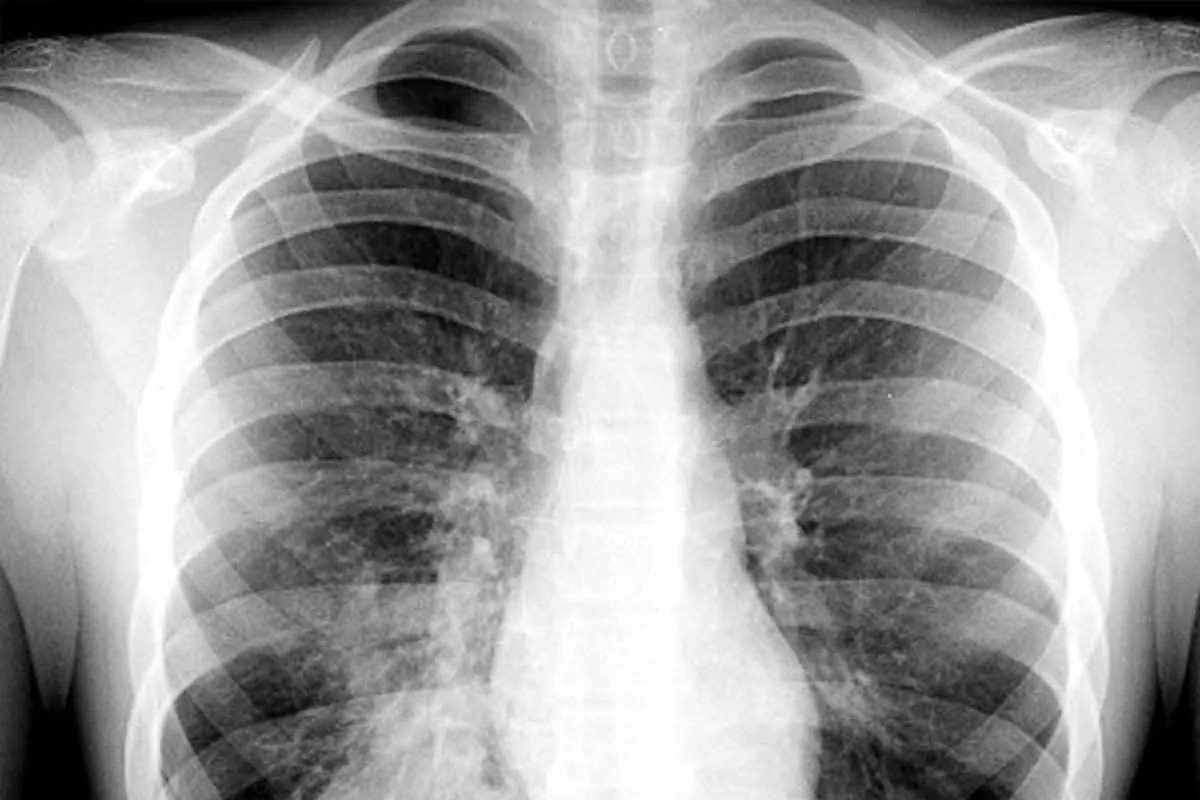

<p style="line-height:normal;">Маммологическое обследование (check-up) рака молочной железы — это общий термин для обозначения различных методов обследования молочных желез, используемых для раннего выявления признаков рака до его прогрессирования.<span style="font-size:12.0pt;font-family:'Times New Roman',serif;"> </span></p><div id="gtx-trans" style="position:absolute;left:755px;top:37.6667px;"><div class="gtx-trans-icon"></div></div>

Молодеет возраст обнаружения рака груди. Поэтому эксперты рекомендуют начинать клинические осмотры груди с 30 лет.<div id="gtx-trans" style="position:absolute;left:-29px;top:-24px;"><div class="gtx-trans-icon"></div></div>